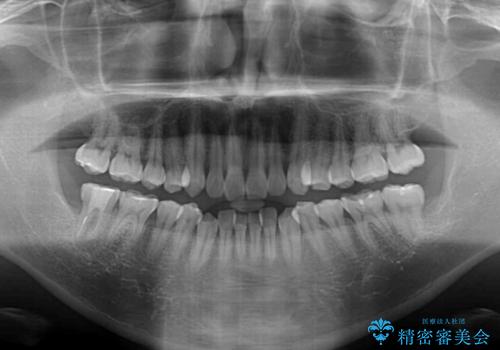

- 上下顎歯列のデコボコを改善したいとのことで来院された患者様です。

自己管理の大変なインビザラインや、目立つ表側のワイヤー矯正は避けたいとのことで、

上顎だけ裏側装置のハーフリンガルにて矯正しました。